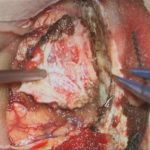

下垂体腫瘍

頭蓋内腫瘍摘出術

No.’22_98 摘出 前

No.’22_98  摘出 中

No.’22_98 摘出 後